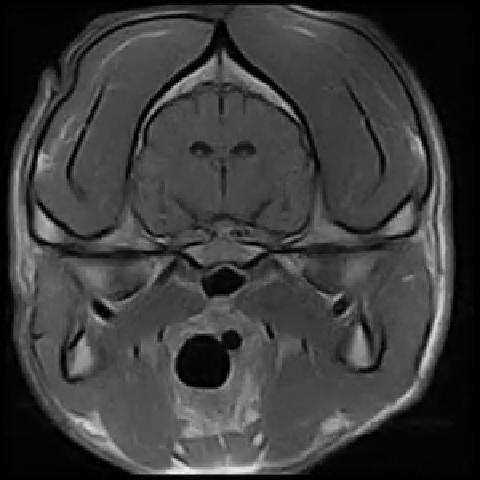

Vet-MR Clinical Images